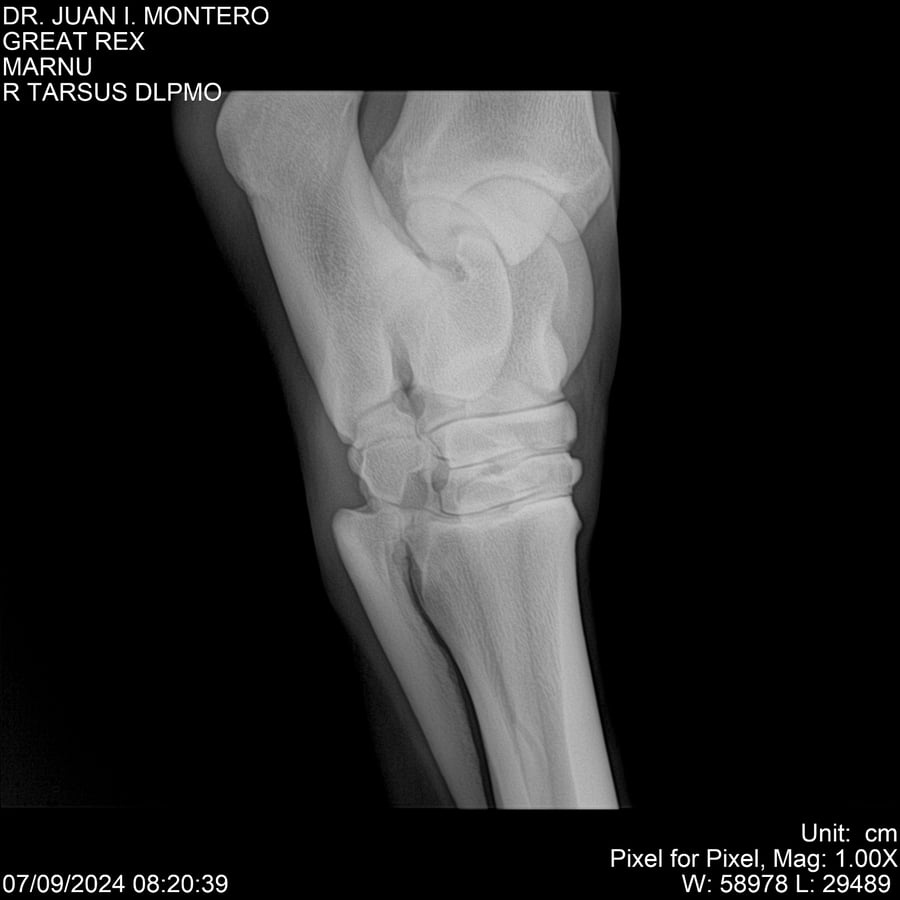

LOTE 4, GREAT REX Lote Anterior Volver al remate Lote Siguiente Ficha Contacto Montevideo - Ficha del Lote Identificador: #282518 Categoría: Yeguarizos Montevideo - 66 Visualizaciones ClicData Contacto Empresa: Abelenda N. R., Walter Hugo Nombre*: Teléfono* : E-mail* : Mensaje Enviar Registrese gratis Este contenido Exclusivo está disponible sólo para usuarios registrados Ingresar